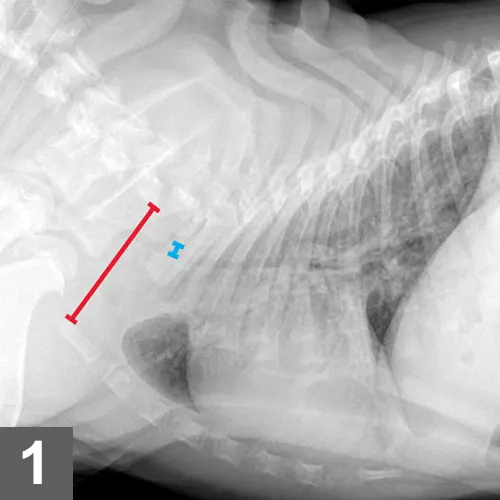

FIGURE 1

Radiograph demonstrating hypoplastic trachea in a bulldog puppy. The thoracic inlet (red line) and tracheal diameter (blue line) are shown.

Radiographs should be evaluated for the presence of hypoplastic trachea (defined as a ratio of tracheal diameter to thoracic inlet height of less than 0.13 for bulldogs and 0.16 for other brachycephalic breeds; Figure 1),13 bronchial collapse, bronchiectasis, pneumonia, pulmonary edema, cardiac chamber dilation, and hiatal hernia (rare). Lung assessment can be challenging because of the dorsoventrally compressed anatomy and difficulty in obtaining a true inspiratory film.